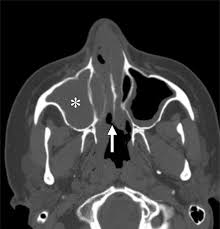

Granulomatous Disease In The Head And Neck Developing A Differential Diagnosis Radiographics